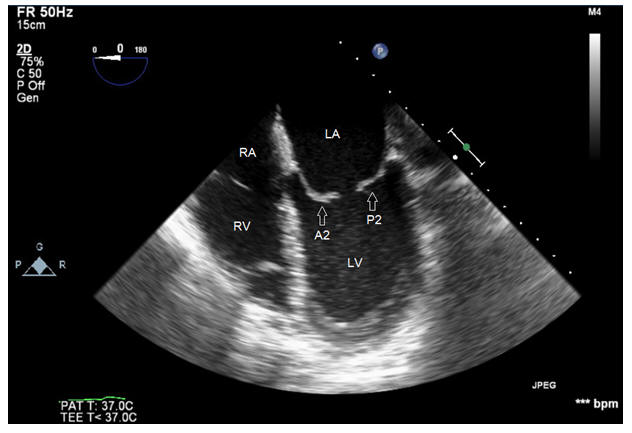

The Road To mitral valve Repair With Live 3D Transesophageal ...

The road to mitral valve repair with live 3D transesophageal echocardiography (TEE) echocardiogram of the mitral valve. Patients with mild or moderate mitral regurgitation that does not affect left ventricular Figure 1. 2D echocardiogram ... Get Doc

echocardiogram : Flail mitral valve With Severe mitral ...

Flail mitral valve , posterior leaflet(chordal rupture) with severe mitral regurgitation and annular calcification.apical 4 chamber view ... View Video